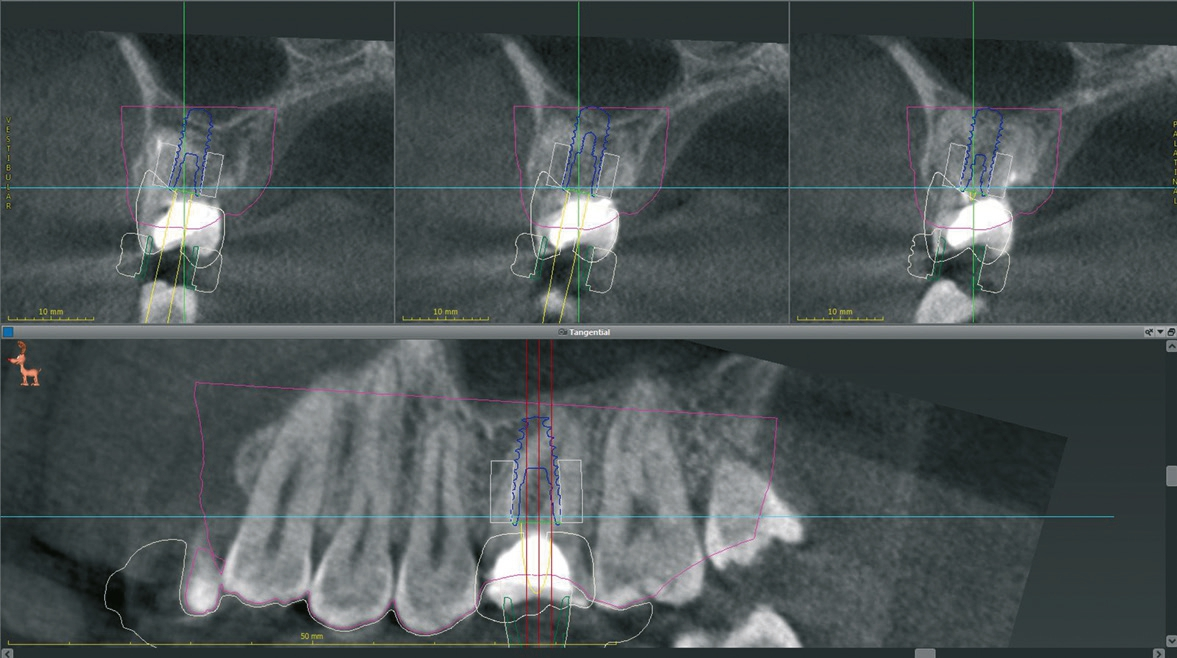

Ein 21-jähriger Patient stellte sich mit einer Perkussionsempfindlichkeit in regio 26 vor. Die klinische Untersuchung zeigte einen tiefzerstörten Zahn 26, dessen gesamte palatinale Wand tief fraktruiert war. Die Frakturgrenze verlief dabei weit unter dem palatinalen Zahnfleischrand (Abb. 1). Nach Erstellung eines Orthopantomogramms und einer radiologischen Einzelzahnbildaufnahme war eine längliche Verschattung am Apex der palatinalen Wurzel des Zahn 26 zu erkennen (Abb. 2), die den Verdacht einer überinstrumentierten Wurzelkanalaufbereitung der palatinalen Wurzel und einer Überstopfung des Füllmaterials bestätigte (Abb. 3). Nach konservierender Theapie wurde die Indikationsstellung für die Extraktion des Zahnes 26 mit einer Sofortimplantation gestellt. Der Periodontal-Screening-Index wies in allen Sextanten Grad 2 auf. Es folgte die Erstellung einer dreidimensionalen Röntgenaufnahme (Orthophos XG 3D, Dentsply Sirona, Bensheim) zur virtuellen Planung der Implantatposition. Die operative Planung erfolgte in der Planungssoftware coDiagnostiX 9.5 (dental wings, Montreal, Kanada) (Abb. 4).

Nach der Präparation des Weichgewebes wurde ein Mukoperiostlappen mit Hilfe der Instrumentenspitze PR2 (Piezosurgery, Mectron, I-Genua) vorsichtig präpariert, um eine suffiziente Deckung der Wunde zu gewährleisten (Abb. 9 und 10). Nach Vorbereitung des Weichgewebes wurde die 3D-gedruckte Bohrschablone auf den Zahnbogen gesetzt und ein Führungsschlüssel mit 2 mm Durchmesser eingesetzt, durch den ein Osteotom einführt wurde, um eine Führung für den nachfolgenden Trepanbohrer in den Knochen kondensierend zu präparieren (Abb. 11). Entlang des Führungskanals wurde das Bett für den allogenen Knochenring (maxgraft bonering; botiss biomaterials GmbH, Berlin) trepaniert (Abb. 12). Der allogene Knochenring wurde extraoral passgenau zugeschnitten und anschließend in die Extrationsalveole platziert (Abb. 13 und 14). Mittels eines breiten Osteotoms wurde der Knochenring samt basalem Knochensegment schablonengestützt nach apikal in den Sinus maxillaris verschoben. Ein parallelwandiges Implantat (Bone Level Roxolid, SLActive, Straumann) mit einem Durchmesser von 4,1 mm und einer Länge von 10 mm wurde zentral in den positionsstabilen Knochenring primärstabil inseriert, mit einer Fixierungkappe (Durchmesser 5,5 mm) versehen und die umliegende Extrationsalveole mit granulärem bovinem Knochenersatzmaterial ausgefüllt (Abb. 15-17). Anschließend wurde die Wunde mit dem Mukoperiostallappen gedeckt und speicheldicht vernäht (Abb. 18). Zur postoperativen Kontrolle wurde ein Orthopantomogramm aufgenommen, auf dem keinerlei Verletzungen benachbarter anatomischer Strukturen zu erkennen sind (Abb. 19). Es folgten zwei radiologische Verlaufskontrollen, vier und sechs Monate nach dem Eingriff, ohne Besonderheiten (Abb. 20 und 21).